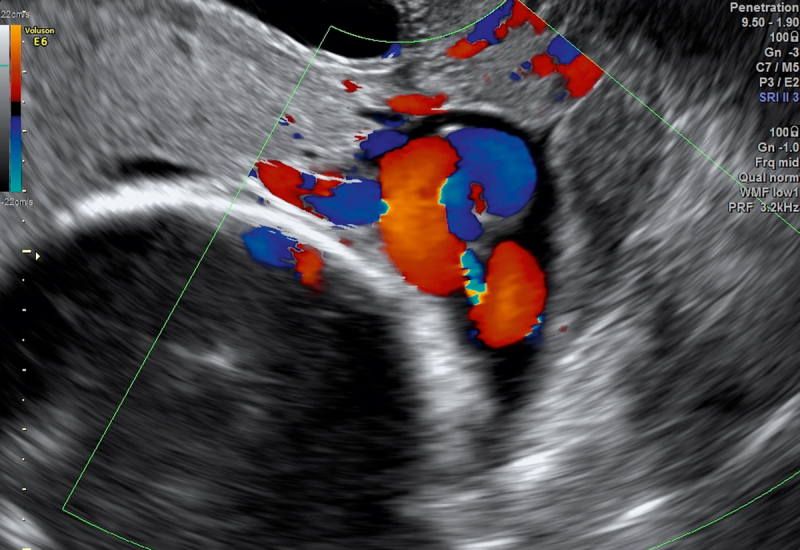

Persistent Funic Presentation And Sonographic Assesment Of The Risk For Umbilical Cord Prolapse.

脐带脱垂风险的持续绒毛表现和超声评估